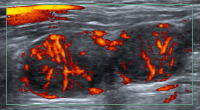

Abbildung 3: Pathologische Gefäßarchitektur. Zwei suspekte Lymphknoten nebeneinander. In jedem Lymphknoten ist das Chaos der Gefäßarchitektur zu erkennen. Plattenepithelkarzinommetastasen.